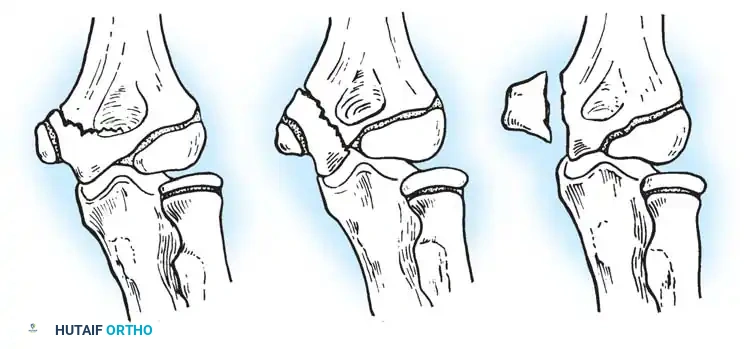

Historically, numerous classifications have been proposed, including those by Vostal, Newman, O’Brien, and Jeffery. In contemporary practice, the Wilkins Classification—which elegantly combines the morphological descriptions of Jeffery and Newman—is the gold standard for guiding surgical decision-making.

Fig. 33-38 Wilkins classification of radial neck fractures. A, Salter-Harris type II fracture. B, Salter-Harris type IV fracture. C, Salter-Harris type I fracture.

The Wilkins Classification System:

* Type A: Salter-Harris type I and II injuries of the proximal radial epiphyses.

* Type B: Salter-Harris type IV injuries of the proximal radial epiphyses.

* Type C: Fractures involving exclusively the proximal radial metaphysis.

* Type D: Fractures occurring iatrogenically when a dislocated elbow is being reduced.

* Type E: Fractures occurring simultaneously in conjunction with an elbow dislocation.

Fig. 33-39 A, Fracture occurring when elbow dislocation is reduced. B, Fractures occurring at time of elbow dislocation.

Fractures can present as angulated, translocated (shifted), or totally displaced. In the context of an elbow dislocation, the proximal fragment may become loose within the joint space or trapped, acting as a mechanical block to reduction.

Fig. 33-40 Examples of angulation, translocation, and total displacement of radial neck fractures.